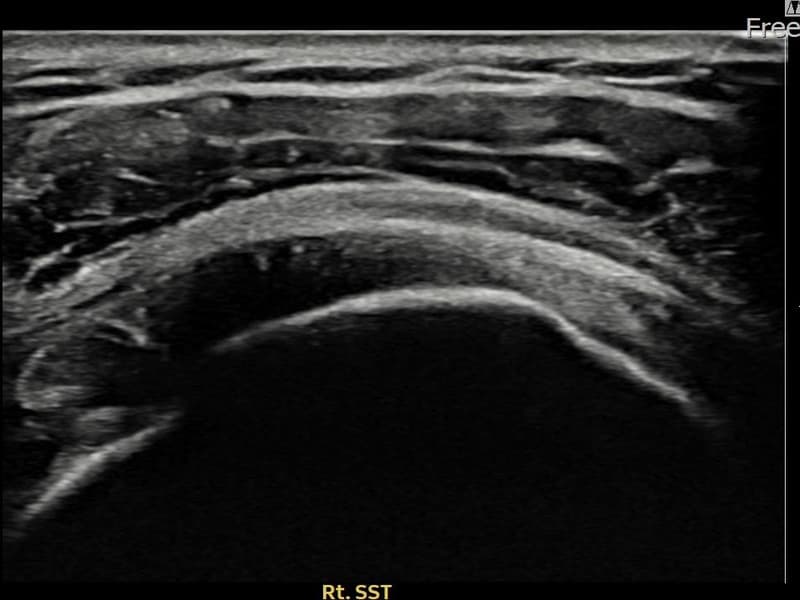

施術前

術前超音波にて右 棘上筋腱 関節面側部分断裂・右肩棘上筋腱のエコー不連続と腱欠損(9mm × 4mm (腱厚の約38%欠損))を確認。術後超音波では断裂部位が再生組織で充填され、腱の連続性回復とエコーパターンの正常化が確認されました。